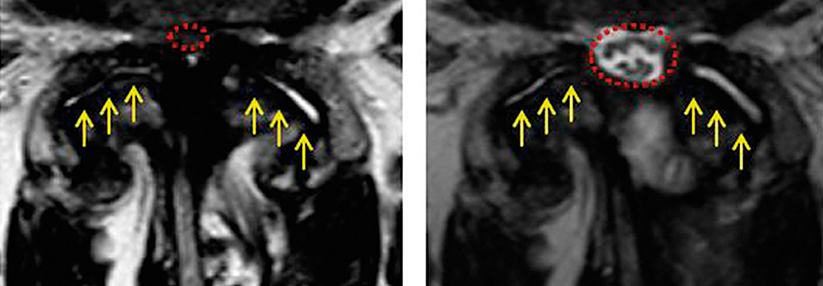

Eine lumbale degenerative Spondylolisthese mit Spinalkanalstenose kann mit oder ohne Fusion* der Wirbelkörper operiert werden.

Laut einer Untersuchung aus Norwegen ist die alleinige chirurgische Dekompression dem kombinierten Eingriff nicht unterlegen. In die Studie hatten Forschende 267 Patientinnen und Patienten mit lumbaler Spinalkanalstenose aufgrund einer Spondylolisthese von ≥ 3 mm eingeschlossen. Die Teilnehmenden im Alter von 18 bis 80 Jahren unterzogen sich entweder einer Dekompression allein (n = 134) oder einer Dekompression mit instrumentierter Fusion (n = 133).